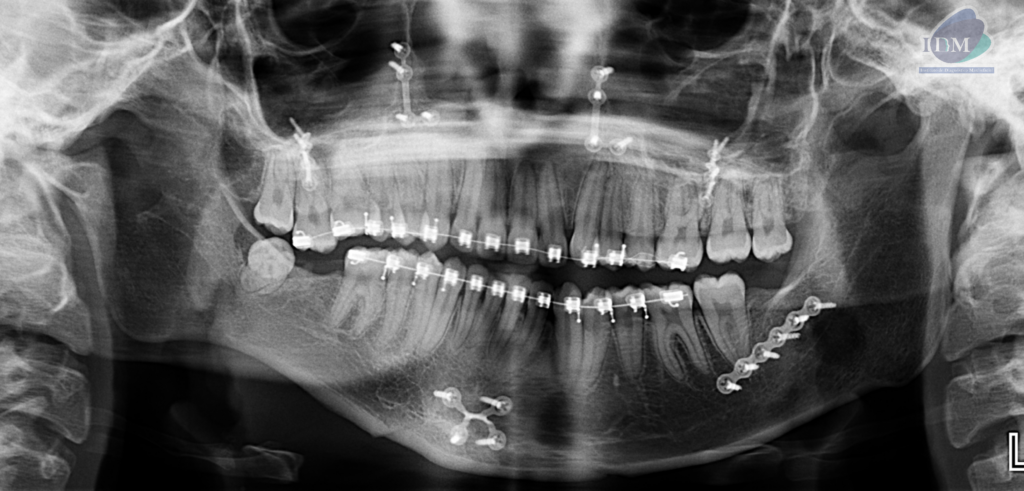

Radiografia Panorámica

A la evaluación de la radiografía panorámica se evidencia múltiples placas con tornillos de fijación bimaxilar así como aparatología de ortodoncia bimaxilar.

Evidenciando una alteración de la morfología de rama mandibular derecha.

Así mismo en la tomografía volumétrica de haz se confirma una elongación por parte de la apófisis coronoides de lado derecho, extendiéndose sobre el borde superior del arco cigomático de ese mismo lado.

- Hiperplasia de apófisis coronoides de lado derecho.